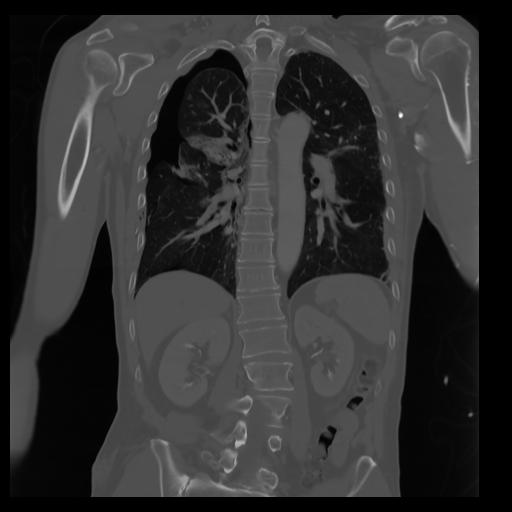

29 CUERPO,CE,Coronal,3.000,CUERPO,Coronal,